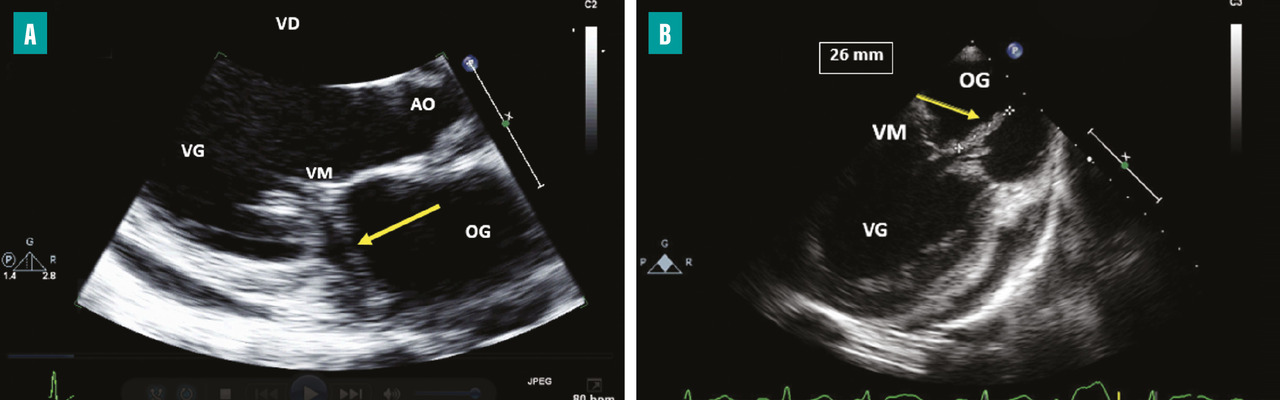

Les accidents emboliques représentent la deuxième cause de mortalité de l’EI. Leur incidence est estimée entre 10 et 50 %.6,7 Ils sont en rapport avec la fragmentation et la migration d’une partie d’une végétation dans la circulation artérielle pour les EI du cœur gauche et dans la circulation pulmonaire pour les EI du cœur droit. Ils sont dominés par les accidents neurologiques, suivis des embolies spléniques, rénales et pulmonaires. Le risque embolique est maximal au début du traitement antibiotique, puis diminue progressivement dans les deux premières semaines de traitement pour devenir minime ensuite.8,9 Dans environ 20 % des cas, l’embolie est cliniquement silencieuse et mise en évidence uniquement sur l’imagerie. Les facteurs prédictifs d’un haut risque embolique dans l’EI sont : la taille de la végétation (haut risque si supérieur à 10-15 mm [fig. 1 ]), sa mobilité et sa localisation sur la valve mitrale, l’EI à Staphylococcus aureus et la non-réduction de la taille des végétations sous traitement antibiotique.6